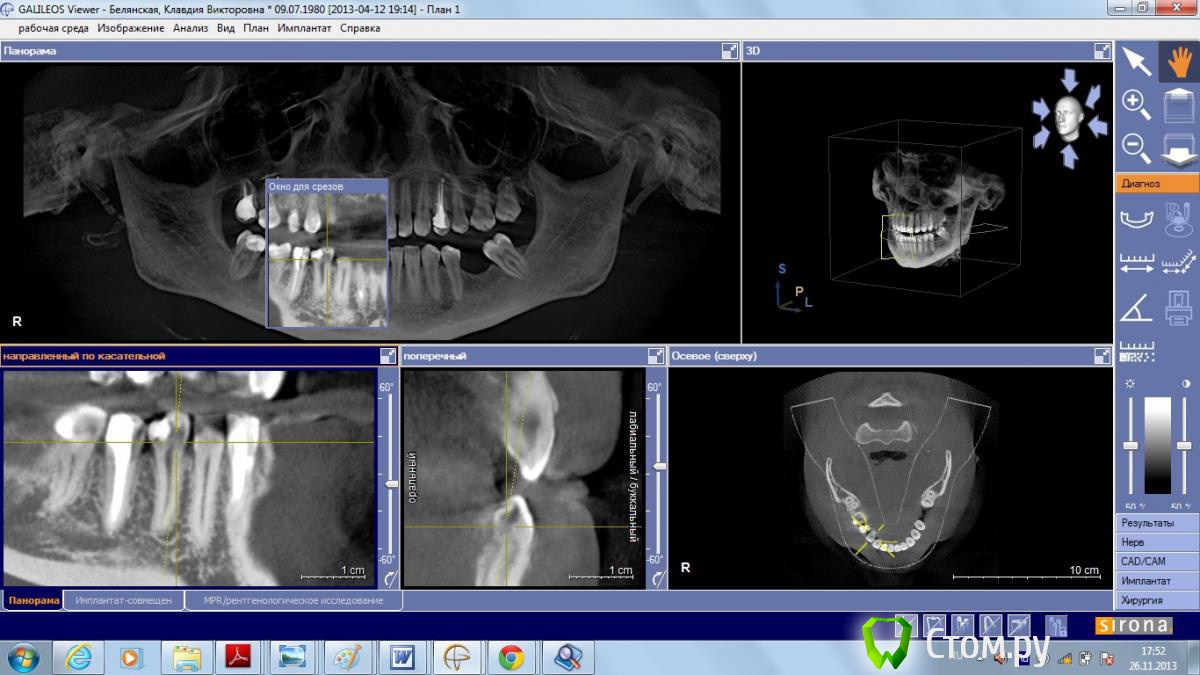

Yniversal Опубликовано 26 ноября, 2013 Поделиться Опубликовано 26 ноября, 2013 Здраствуйте уважаемые коллеги!Хотелось бы узнать ваше мнения по поводу тактики ведения данных пациентов , возможности проведения синус-лифтинга и имплантации.Спасибо 1. 15-продольная фрактура коронки и верхней трети корня.Изменения слизистой пазухи.Выведение ПМ за верхушку.Клиники синусита нет.16 перкуссия "-"2. После кт исследования проведены удаления 25 26 27. Клиника синусита не выражена.Пациент жалоб не предьявляет.3.16 удален несколько лет назад.Клиники со стороны пазухи не выявлено Ссылка на комментарий